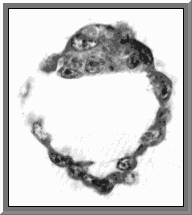

The blastocyst

Within the morula that has reached the uterus, the blastocoel emerges. The wall of this cavity is formed by the trophoblast and the embryoblast The blastocyst hatches from the zona pellucida and penetrates the endometrium by fagocytotic activity of the trophoblast Implantation is completed around the ninth day after ovulation.